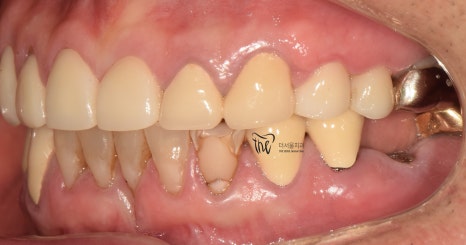

그리고, 지르코니아 크라운을 연결해드리면서

결손부위에 따른 재건은 모두 마쳐드렸습니다.